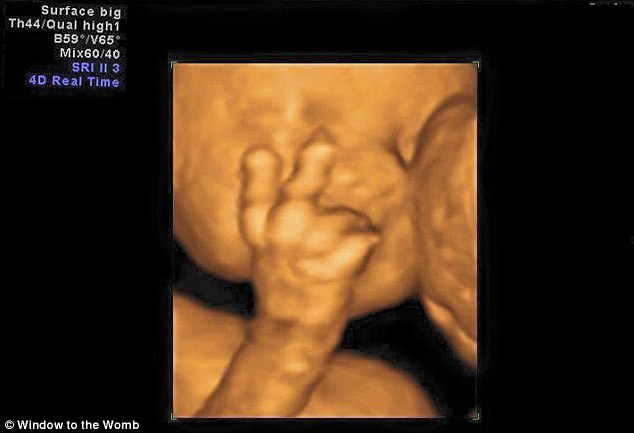

Aimee Ford è andata a fare un’ecografia al settimo mese di gravidanza insieme al marito Russ Worlock. I due hanno raccontato di essere rimasti completamente scioccati dopo aver visto il loro terzo figlio che saluta mostrando due dita vicino al volto. I due hanno raccontato di aver riso: “La nostra ecografia del settimo mese di gravidanza, resterà per sempre indimenticabile. Io proprio non me l’aspettavo” ha detto la donna già madre di due figli: Evelyn che ha 4 anni e che ha partecipato all’ecografia, ed Edward nato nel mese di novembre.

Il feto che saluta la mamma con due dita3